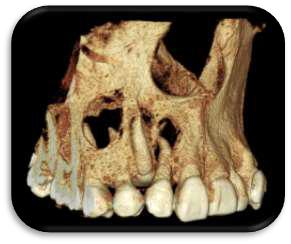

RECONSTRUCCION 3D DE LA ZONA A ESTUDIAR

Las reconstrucciones tridimensionales nos permiten una visualización detallada y precisa de las estructuras vecinas a la pieza retenida, superando las limitaciones 2D de las radiografías convencionales, también ayudara en este caso para la planificación quirúrgica y posterior tratamiento de ortodoncia.

En este caso podemos observar una lesión de diámetro considerable de bordes corticalizados y forma irregular proyectada en el maxilar superior en el cuadrante 1, que se extiende desde distal de la pieza 1.1 hasta distal de la pieza 1.5, desde el tercio apical de las piezas 1.2 – 1.4 y 1.4 por vestibular y desde cervical por palatino. Se evidencia también a la pieza 1.3 retenida desplazada el ápice hacia la cortical palatina y la corona hacia la cortical palatina

CORTES AXIALES

Con la evaluación de la tomografía volumétrica en cortes axiales y transversales se observa la expansión y adelgazamiento de la tabla ósea vestibular y palatina legando a dicha pérdida ósea, también se observa el desplazamiento de la pieza 1 3 la cual se encuentra retenida y desplazada hacia la basal vestibular.

CONCLUSION

CORTES SAGITALES

A nivel de los cortes sagitales y coronal verificamos la extensión de la lesión y evidenciar el desplazamiento de las piezas 1.2 a mesial y 1.4 hacia distal a causa de la retención de la pieza 1.3 y expansión de la lesión

Las neoplasias benignas tienen una etiología y evolución compleja dado que en muchas ocasiones una lesión presenta características similares a otras, lo que daría para pensar que desde el origen hasta la madurez de la lesión hay etapas que se pueden confundir con otras entidades. En base a estos hallazgos se plantean cuatro diagnósticos diferenciales, fibroma osificante, tumor odontogénico queratoquistico, quiste dentigero

Por ello se recomienda en estos casos un estudio histopatológico para confirmar diagnóstico y proceder al plan de tratamiento correcto.